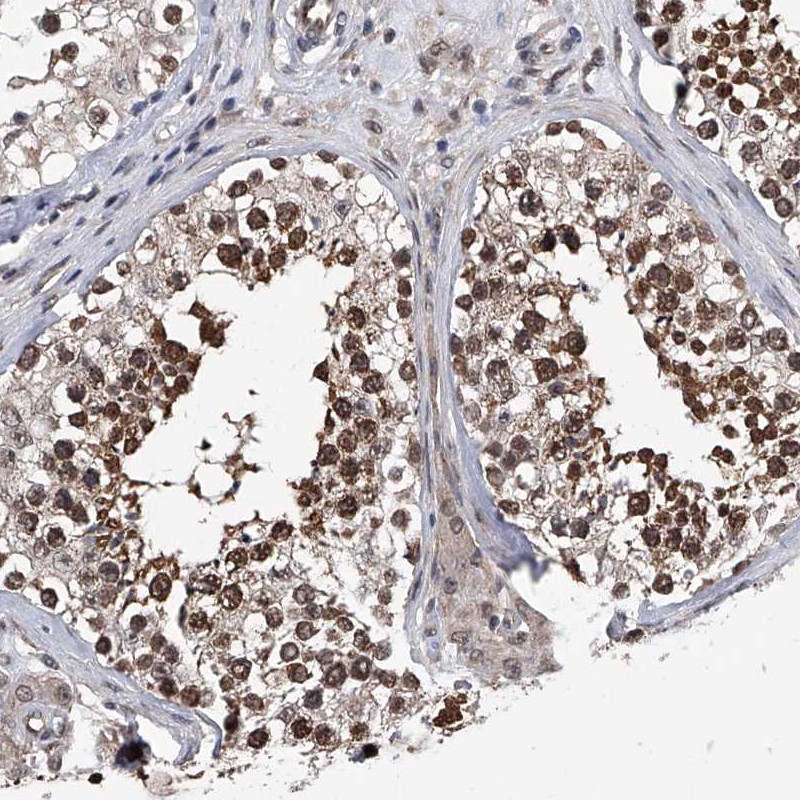

Immunohistochemical staining of human testis shows strong nuclear and cytoplasmic positivity in cells in seminiferus ducts.